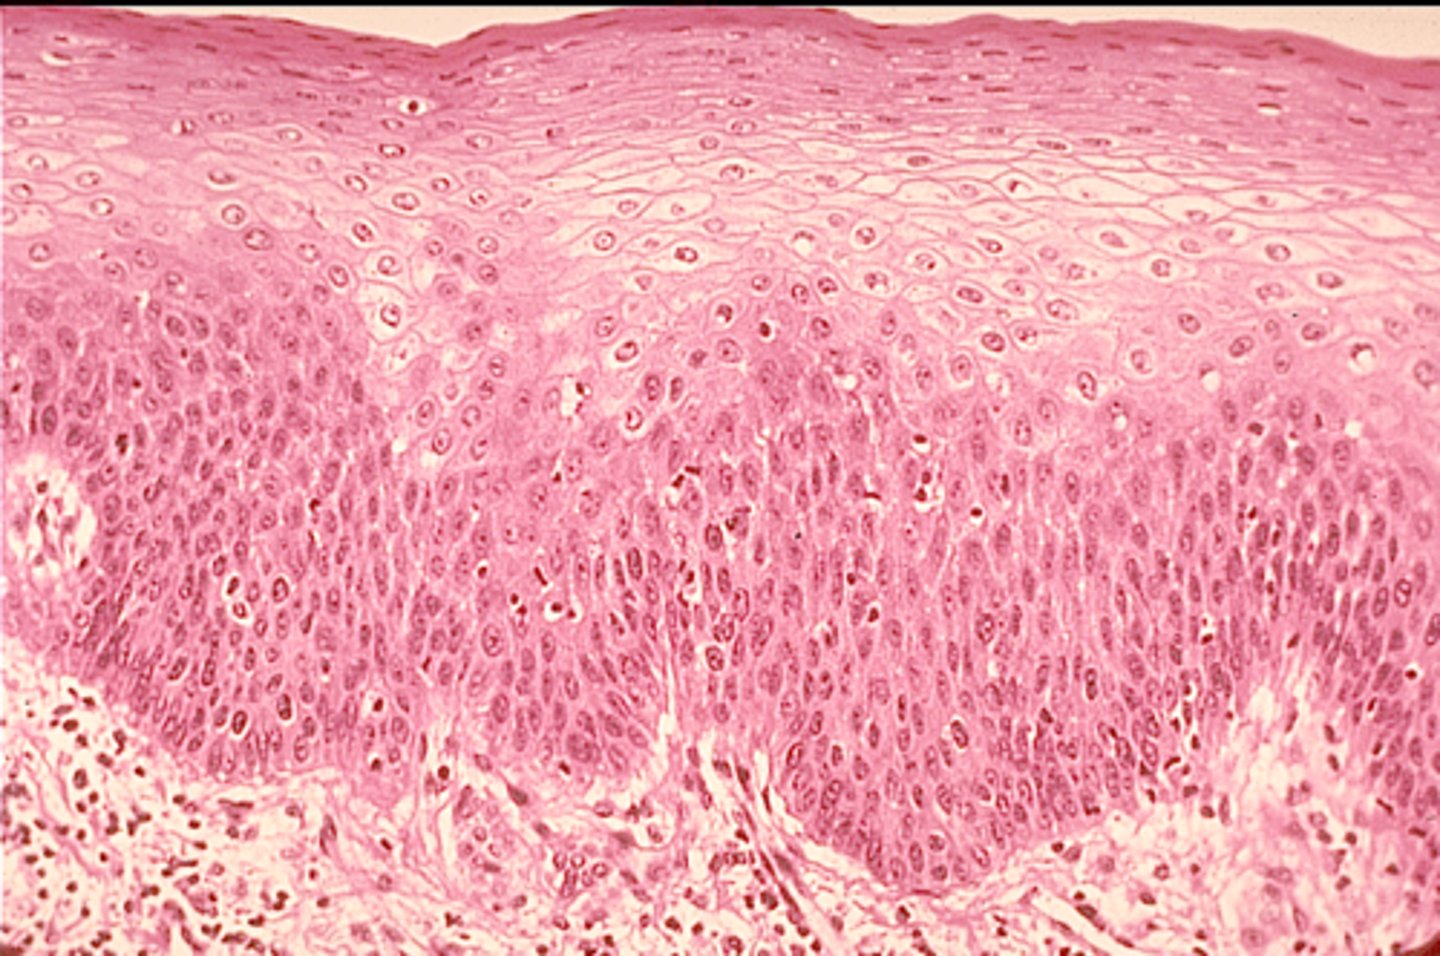

stratified squamous epithelium

Protects underlying tissue in areas subjected to abrasion. Mouth Vagina

Stratum spinosum

Several layers of keratinocytes joined by desmosomes. Thick bundles of intermidate filaments made of pre-keratin

Stratum basale

Deepest epidermal layer